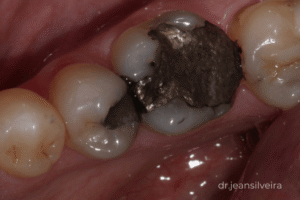

Cáries

Quando há perda de estrutura, a restauração é necessária para recuperar a função e a estética do dente.

Qualidade dos materiais e da técnica

Hoje utilizamos materiais modernos que são colados ao dente por meio de sistemas adesivos.

Esse processo funciona como uma ligação entre o dente e a restauração.

Porém, é um procedimento altamente técnico e sensível.

Falhas nessa etapa podem comprometer a durabilidade.